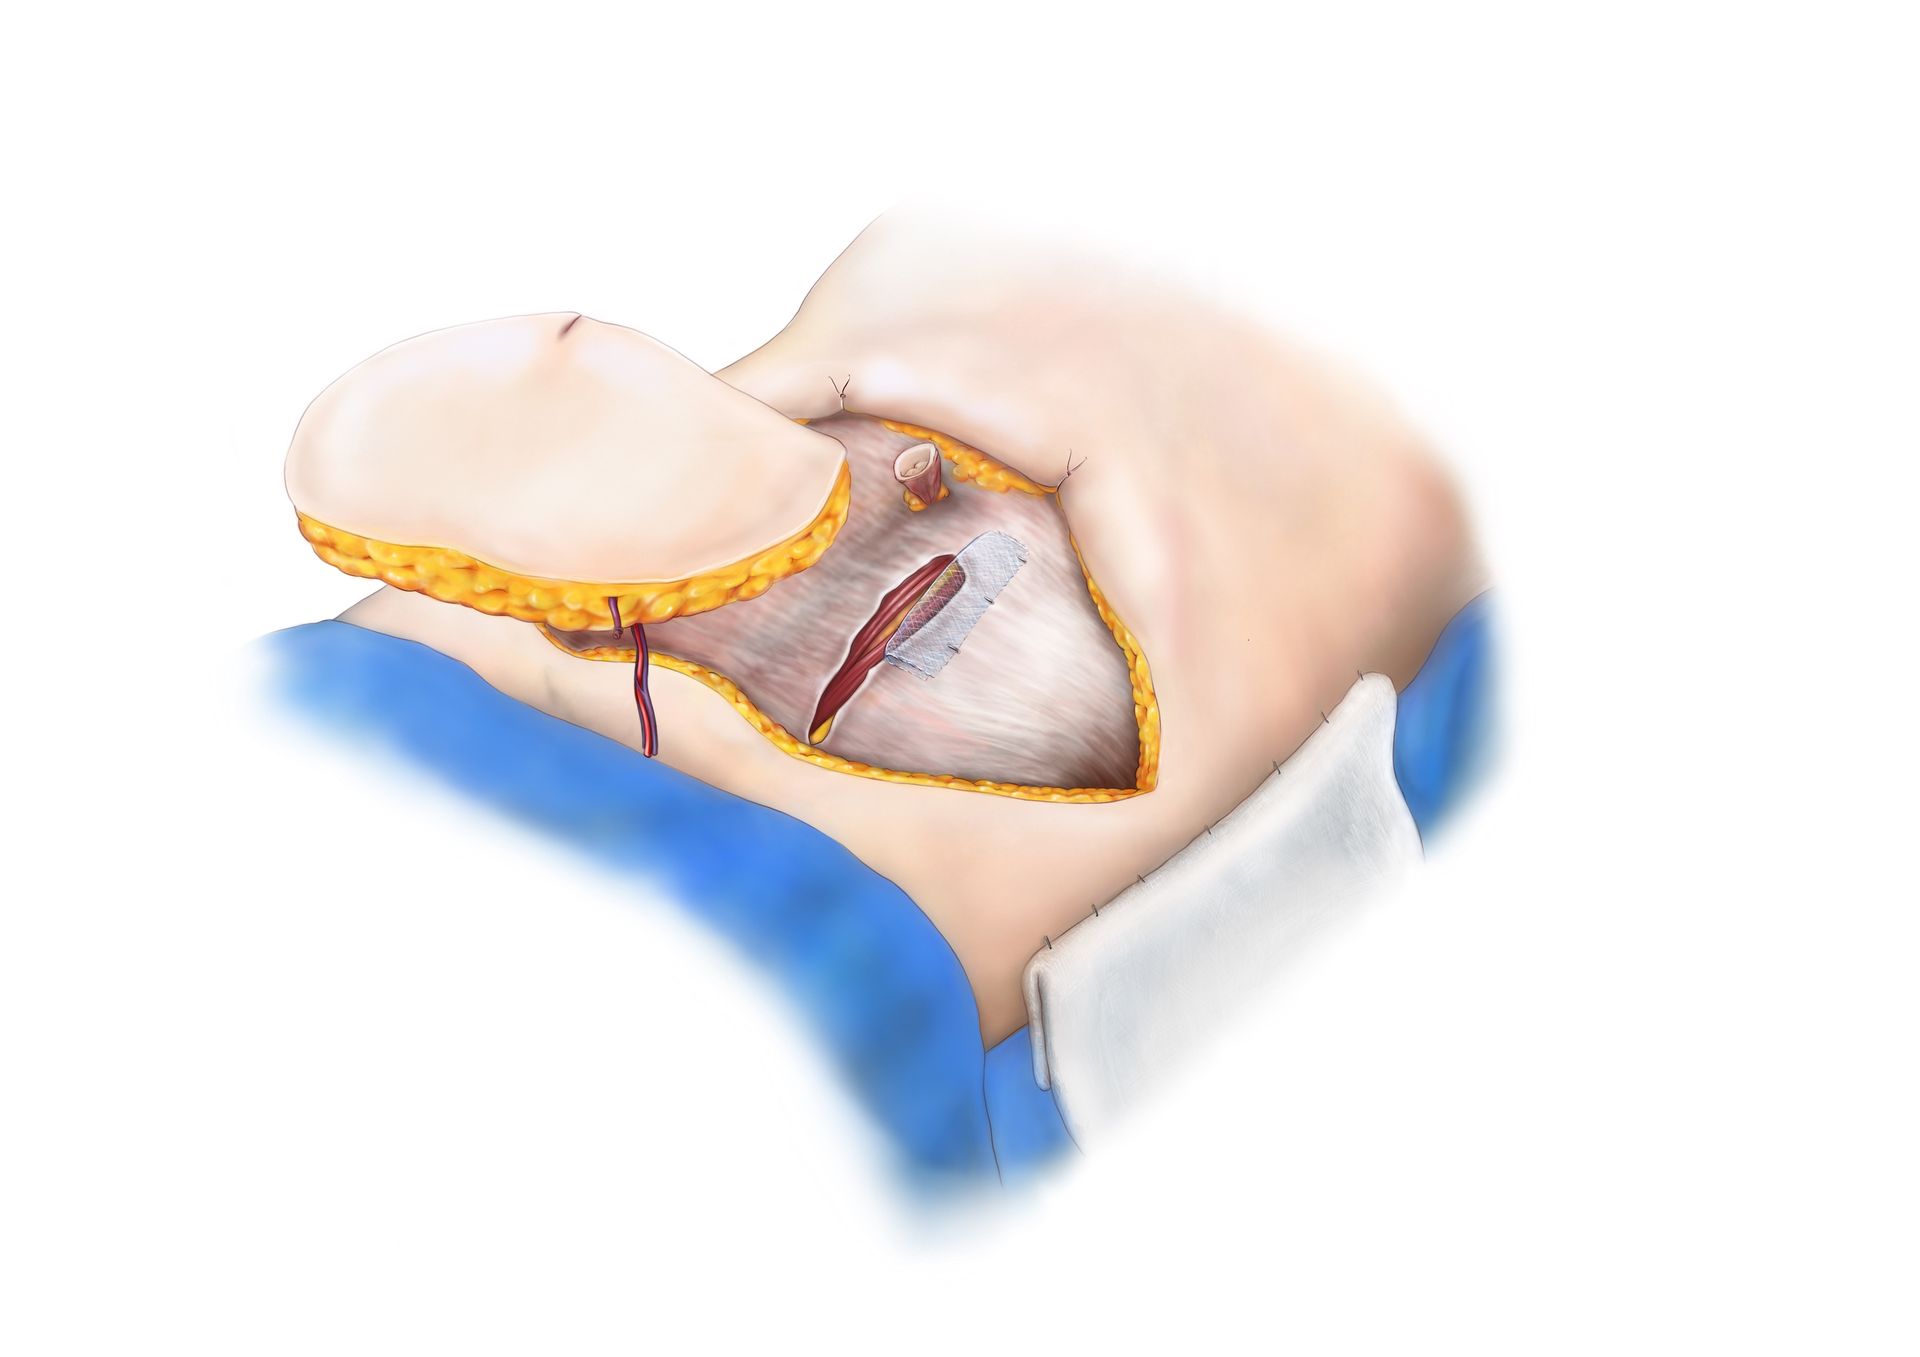

DIEP flap naar borstkas

De DIEP flap wordt verplaatst naar de borstkas. Men gaat nu met microchirurgie het bloedvat van de DIEP flap hechten aan het bloedvat naast het borstbeen. Hierdoor krijgt de DIEP flap terug een bloeddoorstroming waardoor deze kan overleven.

Sluiten buik

De buikregio kan nu gesloten worden. De insnede in de spierfascia werd gesloten en de bovenbuik wordt "ondermijnd" om een vlotte sluiting te bekomen. De navel kan bewaard worden of verwijderd worden. Een nieuwe navel kan dan later gereconstrueerd worden.